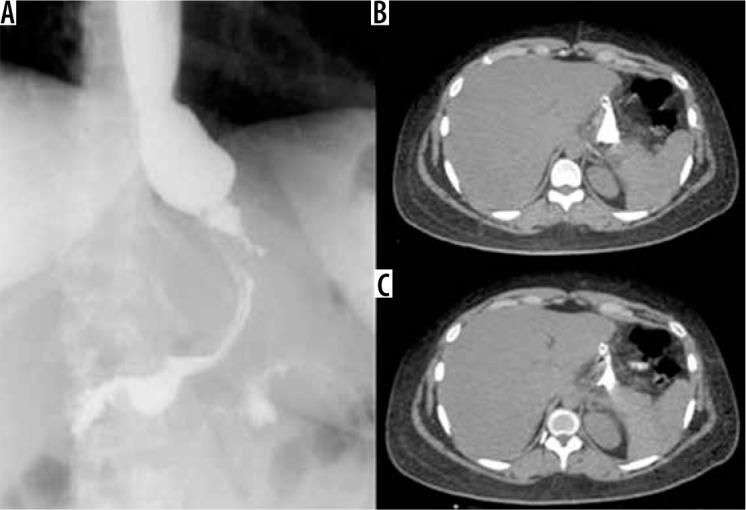

诊断性影像学在减重手术急性并发症诊断中的应用

Diagnostic imaging in the diagnosis of acute complications of bariatric surgery.

The aim of study is to identify the frequency of acute complications and imaging findings at gastro-intestinal transit (GI) and computerised tomography (CT) in a group of obese patients who developed clinical suspicion of acute complications (painful and meteoric abdomen, nausea, vomiting, fever, intestinal blockage) in post bariatric surgery.

MATERIAL AND METHODS

We retrospectively review 954 obese patients who underwent bariatric surgery between 2013 and 2019. The study included 72 patients who developed clinical suspicion of acute complications (painful and meteoric abdomen, nausea, vomiting, fever, intestinal blockage) within 6 days of bariatric surgery of sleeve gastrectomy, gastric banding, gastric bypass with Roux loop confirmed by CT, and who underwent a gastrointestinal transit before the CT examination.

RESULTS

GI exam allowed visualisation of 58% of complications. Analysing the data for each surgical technique, 46 post-operative complications were found involve gastric banding. The most frequent was bandage migration (26 cases, 56 %), identified in all cases at GI transit and then confirmed on CT.

CONCLUSIONS

The study suggests that CT should be used to clarify all doubtful or clinically discordant GI transit exam results. The participation of a radiologist in qualification and post-operative evaluation is important for bariatric surgery patients.

本研究旨在确定一组肥胖患者在接受减重手术后出现急性并发症临床疑似症状(腹痛、腹胀、恶心、呕吐、发热、肠梗阻)时,胃肠道造影(GI)和计算机断层扫描(CT)检查中急性并发症的发生率及影像学表现。

材料与方法

我们回顾性分析了2013年至2019年间接受减重手术的954例肥胖患者。该研究纳入了72例在袖状胃切除术、胃束带术、Roux袢胃旁路术后6天内出现急性并发症临床疑似症状(腹痛、腹胀、恶心、呕吐、发热、肠梗阻)且经CT证实,并在CT检查前进行了胃肠道造影的患者。

结果

GI检查能够发现58%的并发症。分析每种手术技术的数据,发现46例术后并发症与胃束带术有关。最常见的是束带移位(26例,56%),所有病例在GI造影时均被发现,随后经CT证实。

结论

该研究表明,对于所有可疑或临床结果不一致的GI造影检查结果,均应使用CT进行明确。放射科医生参与减重手术患者的术前评估和术后评估非常重要。